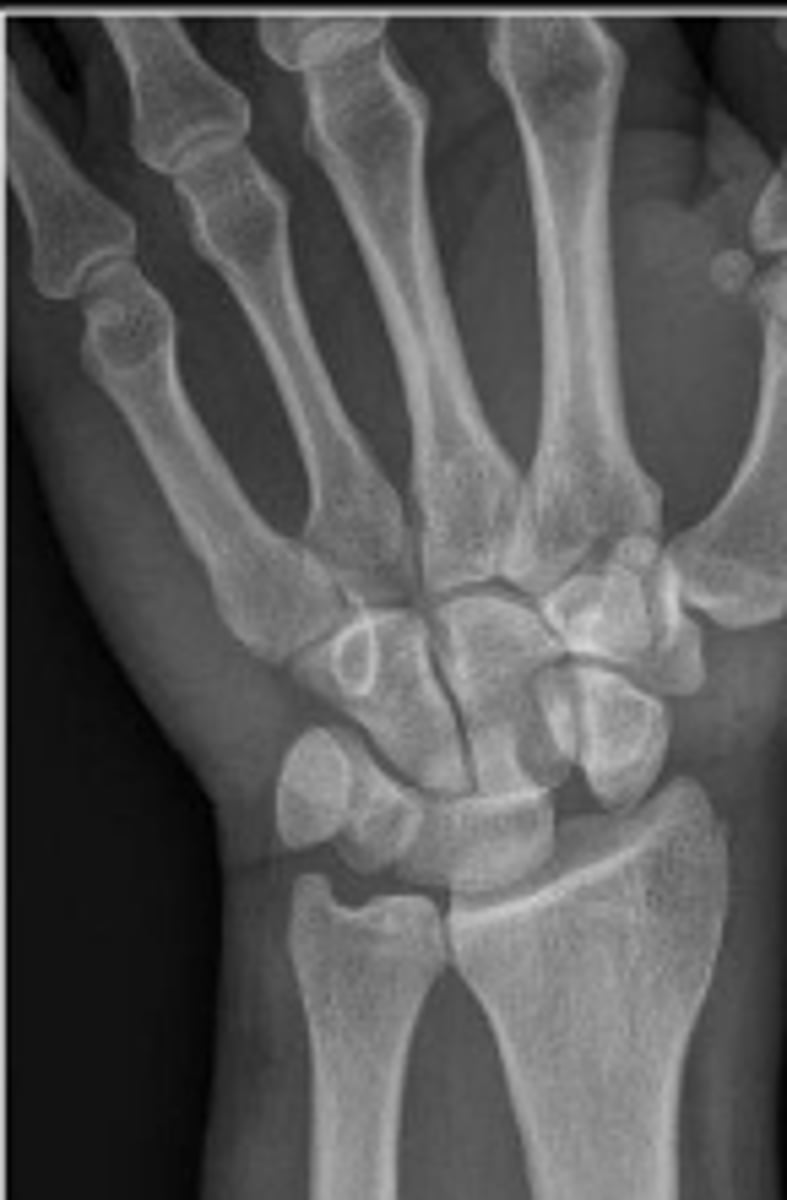

PA wrist

What radiographic view are the

carpal joint spaces assessed?

1-2mm

What is the normal range for the carpal joint spacing?

No

The carpal joint space is measured to be 8mm. Is this considered within normal limits

The scapholunate joint space is measured to be 7mm. Is this considered within normal limits?

Injury to the scapholunate ligament

What is the most common cause of carpal instability?

An altered scapholunate angle and/or altered

capitolunate angle and/or altered lunate position

and/or an increased carpal joint space; DISI; VISI

What 2 radiographic signs would indicate carpal instability?

"Terry Thomas" sign

Mechanism of Injury: Fall onto an outstretched hand.

What is the named sign given to widening of the scapholunate spacing?

2mm

What is the upper limit of the normal measurement?